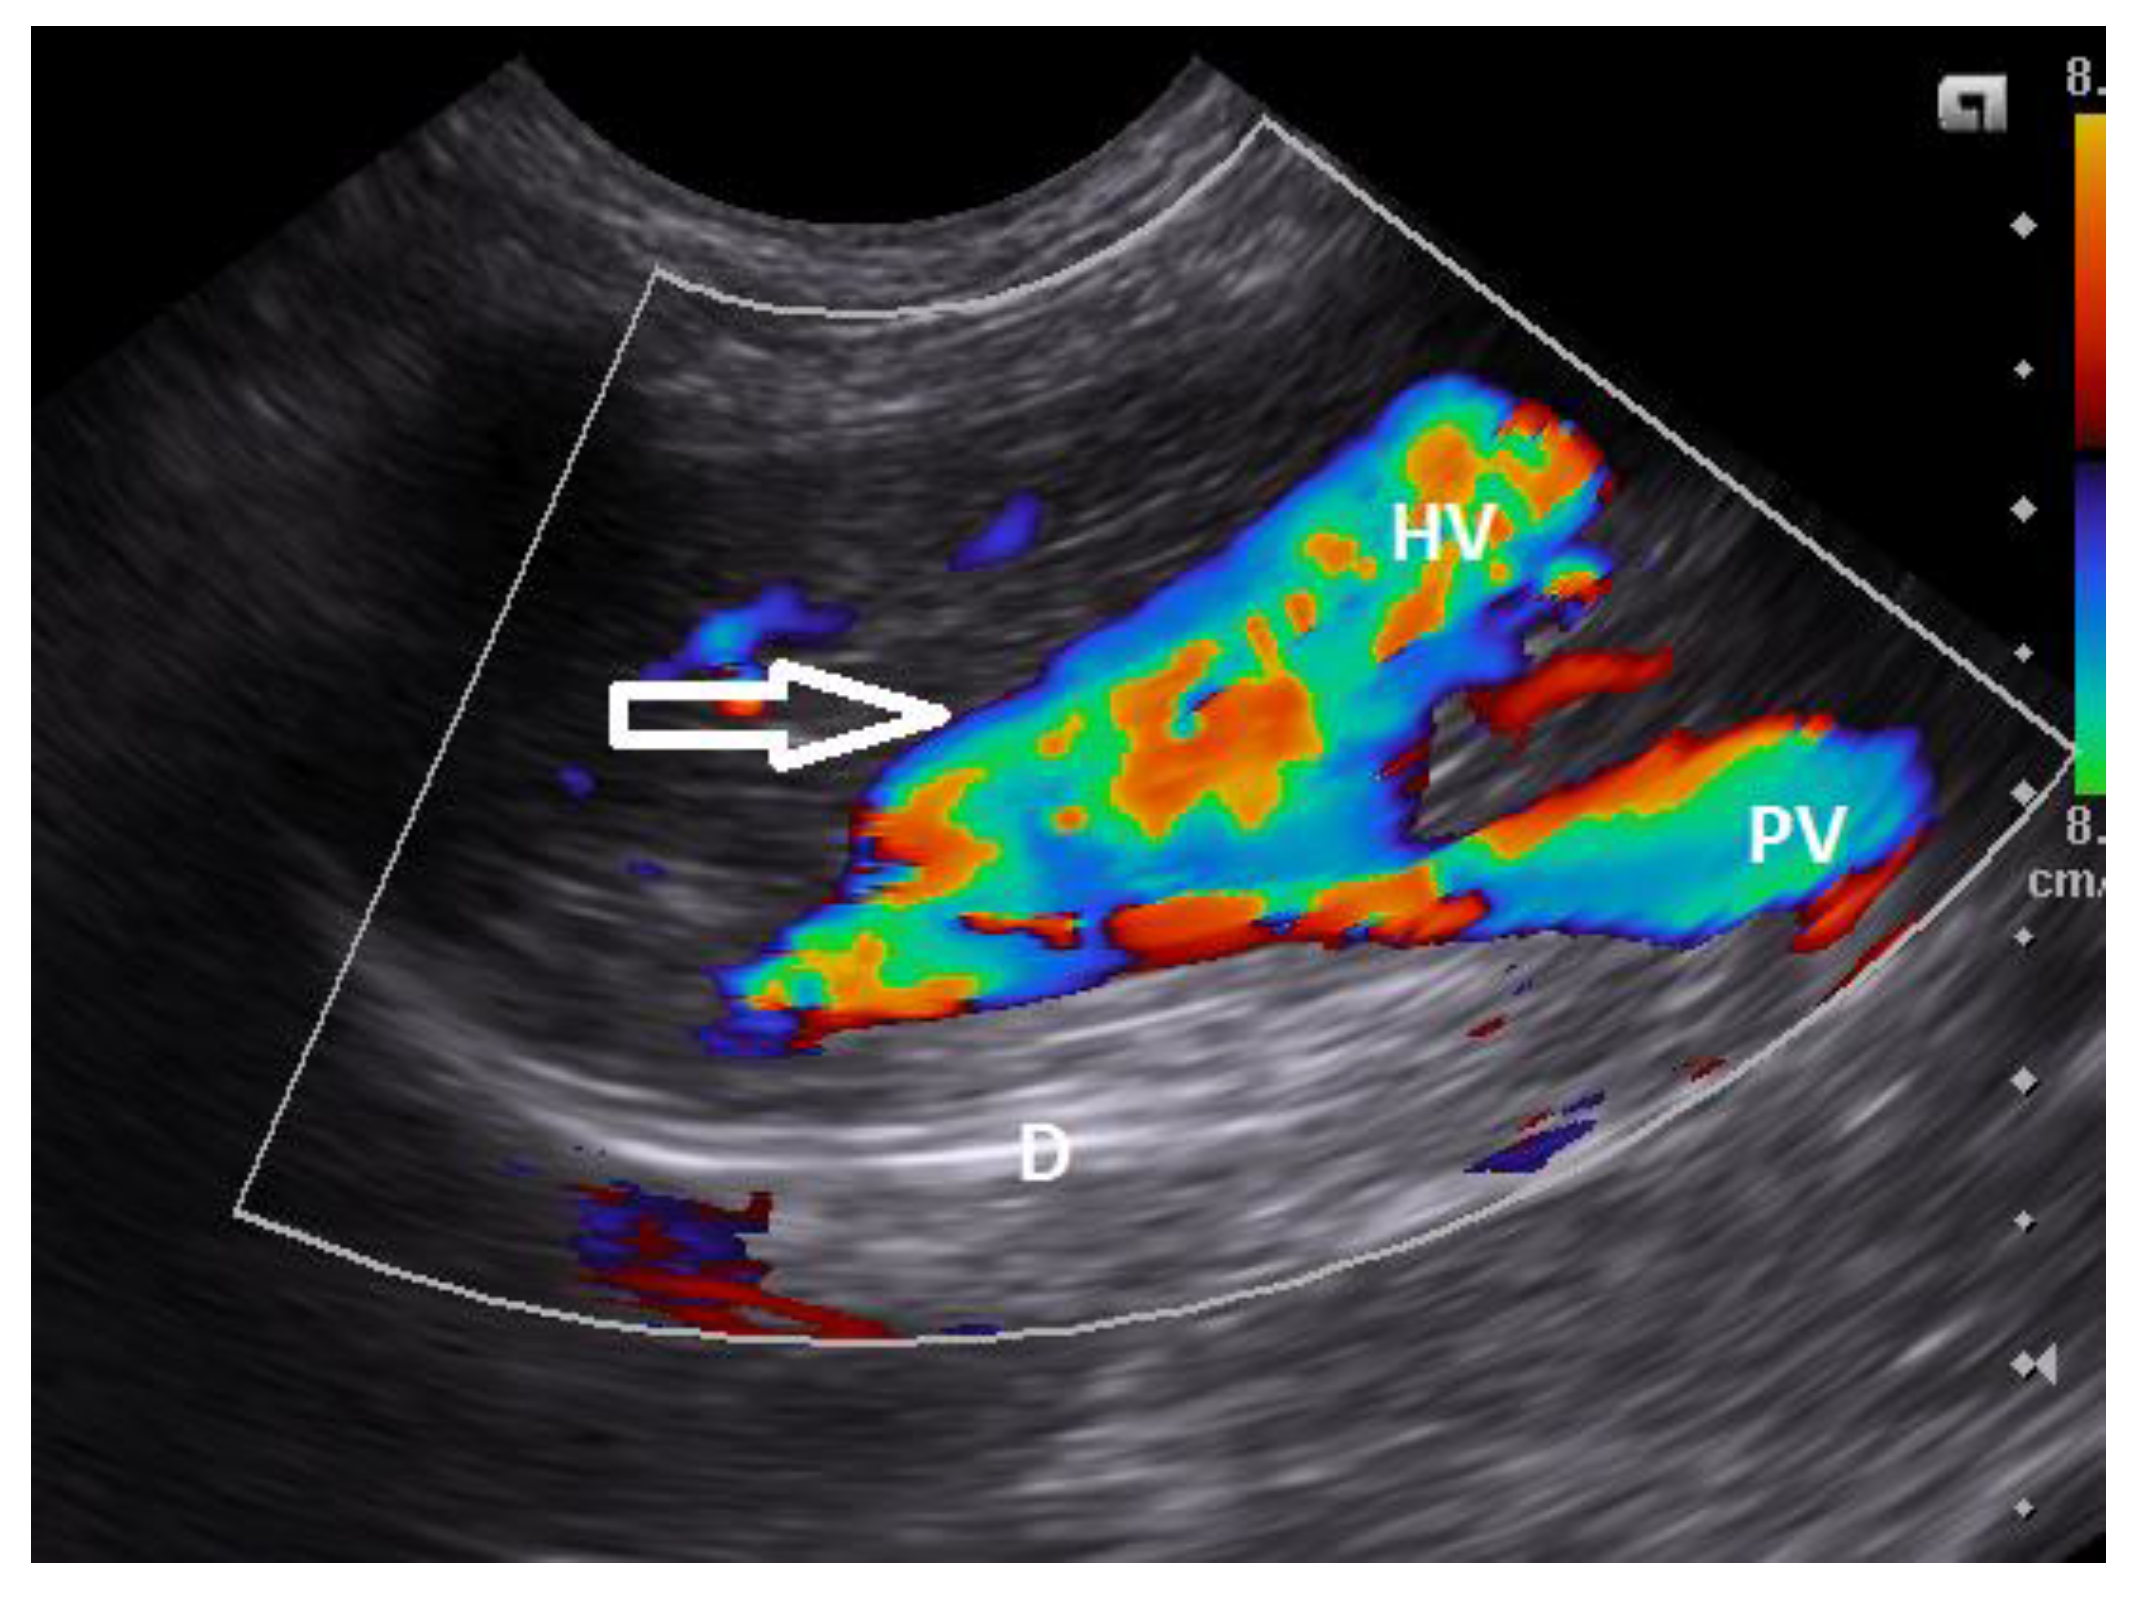

9. Diagnostic Imaging